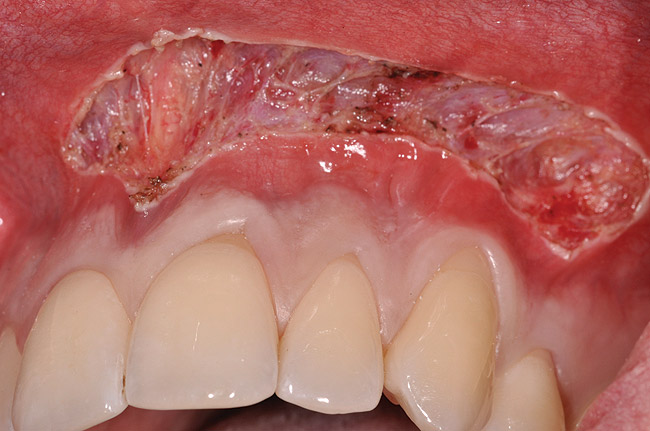

Various procedures to correct deficient gingival contours have been well documented in the dental literature.1,2 Increasing zones of attached gingiva using palatal donor tissue and the free gingival grafting procedure was introduced by Björn almost a half century ago.3 Using palatal donor tissue in the form of a free soft-tissue autograft for root-coverage procedures was reported by Miller.4 Additional procedures were reported using lateral5 or coronal repositioning6-8 of the adjacent attached gingiva via a pedicle flap or the coronal repositioning of previously grafted tissue.9,10 Miller also reported on gingival grafts placed over root surfaces to correct areas of deep-wide gingival recession.11 Further surgical advancements led to the use of subepithelial connective tissue from the palate to obtain root coverage.12-14 Figure 1 shows the pretreatment view of a mandibular central incisor, and Figure 2 depicts the post-treatment view of the site treated with a subepithelial connective tissue graft harvested from the patient’s palatal tissues.